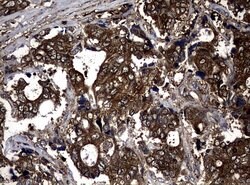

| Immunocytochemistry, Immunofluorescence, Immunohistochemistry (Paraffin) | |